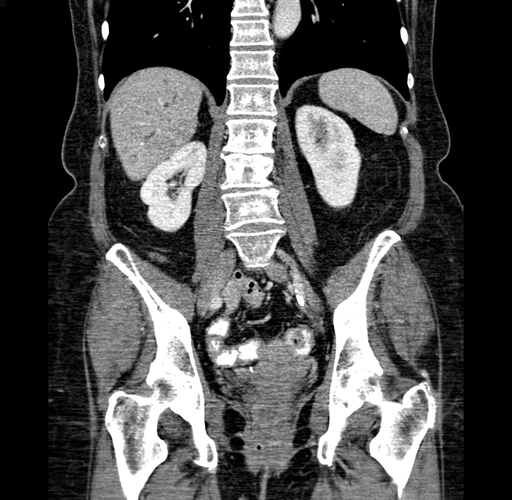

Pre-Chemo: Coronal Venous